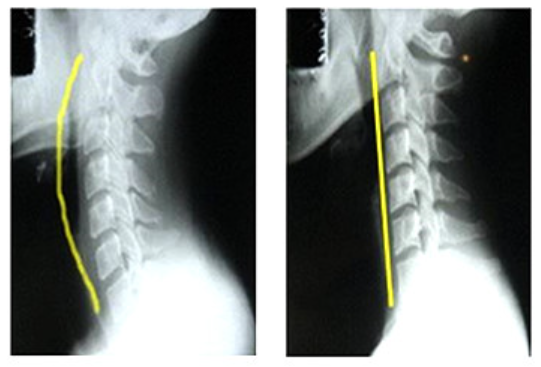

5년전에 목이 너무 아파서, 정형외과에 가서 엑스레이를 찍어 보았습니다.

그리고 의사선생님께서는 '일자목 입니다. 컴퓨터 많이 하시나봐요!' 라고

말씀하셨습니다.

원래 아래와 왼쪽그림같이 c 커브르 그려야 하는데

저는 오른쪽의 그림처럼, 일자의 목뼈 모습이 보이고 있었습니다.